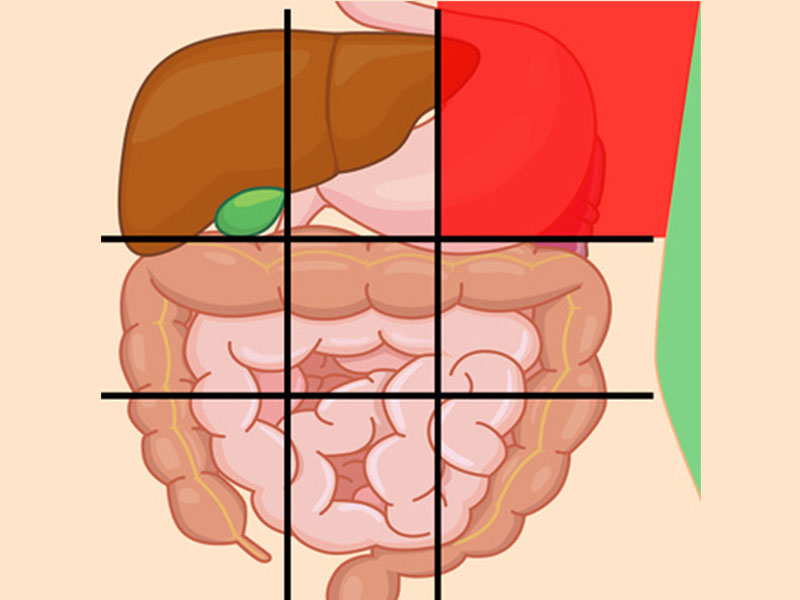

درد شکم در نواحی مختلف نشانه چیست؟

محل درد در شکم ممکن است سرنخی برای علت آن درد باشد که در زیر به بررسی آنها میپردازیم:

درد بالای شکم نشانه چیست؟

این ناحیه شامل لوزالمعده و بخشی از روده کوچک میباشد.

- پانکراتیک (التهاب لوزالمعده)

- فتق اپی گاستریک

- سنگهای صفراوی

- حمله قلبی

- هپاتیت (التهاب کبد)

- ذاتالریه

درد شکم سمت راست بالا نشانه چیست؟

در این ناحیه از شکم انسان، کبد و کیسهی صفرا قرار دارد، بنابراین معمولاً شایعترین علل درد در این ناحیه مربوط به این دو اندام میباشد.

بعضی از علل درد شکم در این قسمت شامل:

- هپاتیت

- جراحت

- ذاتالریه

- آپاندیس

- التهاب کیسه صفرا